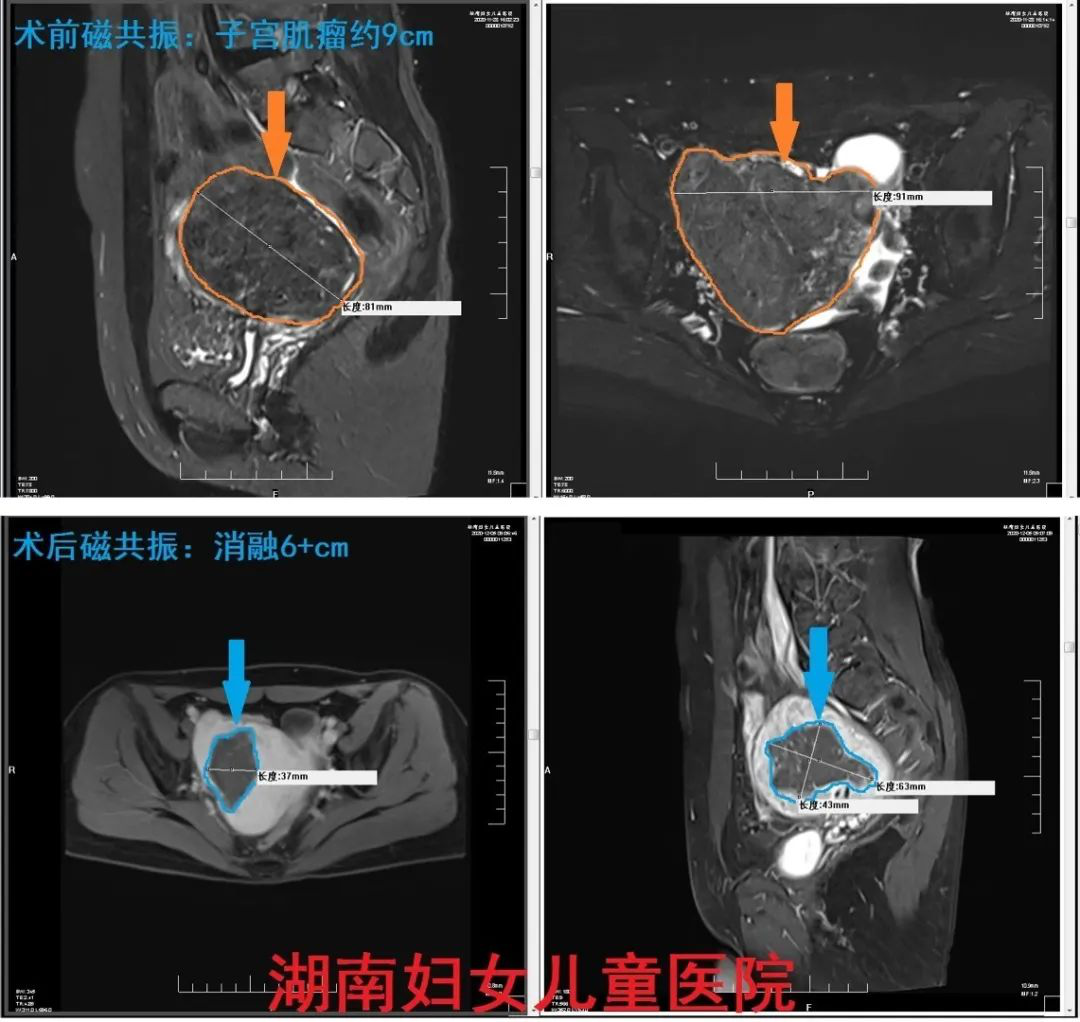

她突然发现子宫肌瘤一年就由5cm增长到了9cm,体积增大了约6倍,乍一看,就像是肚子里多了一个圆滚滚的小柚子。

经过认真研究和一系列严谨细致的检查,周训华团队最终确定和拟定了手术方案,用海扶®️无创治疗技术消融6+cm子宫肌瘤,使肌瘤显著缩小,控制安全阈值内。